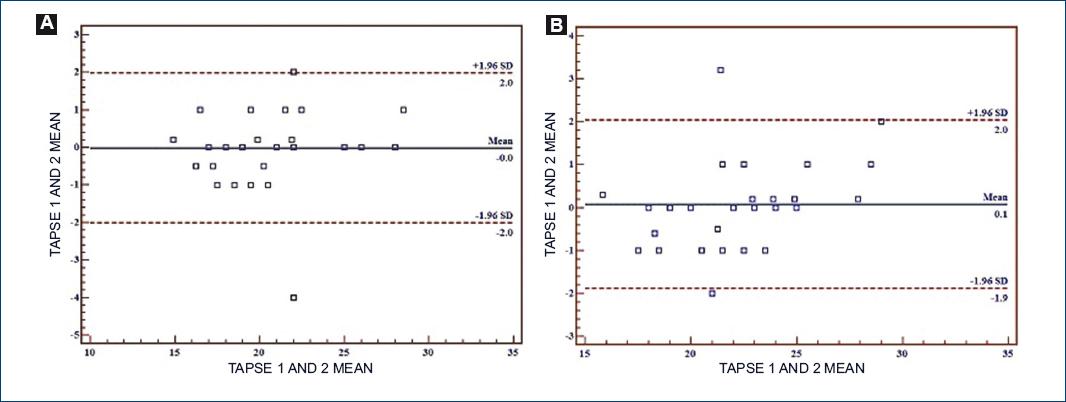

Intra-observer agreement for echocardiographic variables in the dorsal and supine position is shown in table 3. Fig. 3 shows TAPSE as the echocardiographic variable with the lowest variability in both positions.

Table 3 Echocardiographic variables mean difference behavior, bias, intraclass correlation coefficient, and 95% confidence interval in dorsal and prone positions

| TAPSE, mm | 0 (2, –2.0) | 0.976 (0.950, 0.988) | 0.1 (2, –1.9) | 0.974 (0.947, 0.987) |

Intra-subject variability with regard to the enquired indices is small, specifically for TAPSE and the S’-wave, and 100% of the time they could be measured; this small TAPSE variability has already been previously reported in another context22.